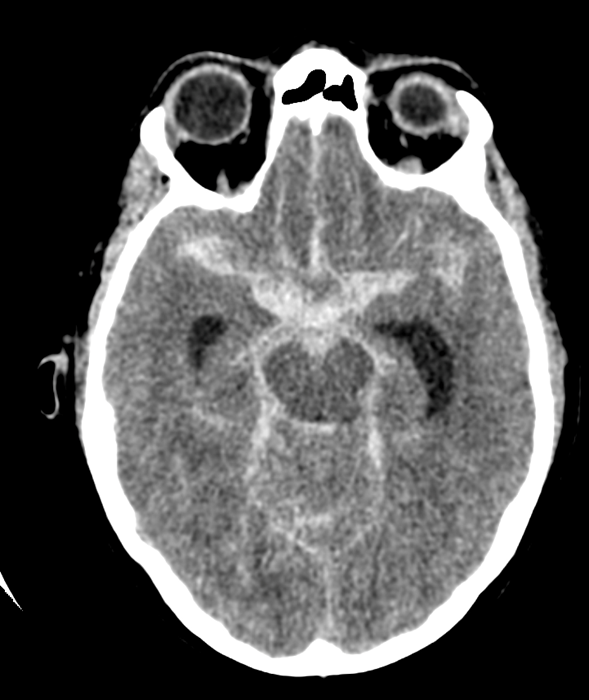

Diagnostic testing. The initial diagnostic workup included a non-contrast computed tomography (CT) scan, which revealed a large volume subarachnoid hemorrhage (Figure 1) centered in the suprasellar cistern along with a small component of intraventricular hemorrhage (Figure 2). The hemorrhage was consistent with a Hunt and Hess Grade 4, Fisher Grade 4 subarachnoid hemorrhage. A computed tomography angiography (CTA) did not reveal any substantial perfusion abnormalities or aneurysms.

Figure 1. A diffuse subarachnoid hemorrhage on the initial non-contrast CT scan.